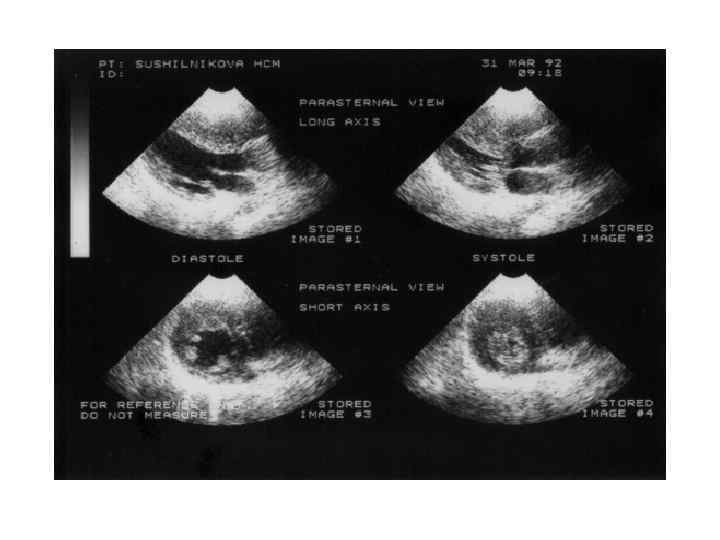

ДКМП Критерии диагноза • Фракция выброса левого желудочка менее 45% • Конечный диастолический размер левого желудочка превышает более, чем на 17% значение, откоррегированное по возрасту и поверхности тела

ДКМП Критерии диагноза • Фракция выброса левого желудочка менее 45% • Конечный диастолический размер левого желудочка превышает более, чем на 17% значение, откоррегированное по возрасту и поверхности тела

ДКМП Симптоматика • Кардиомегалия • Сердечная недостаточность (снижение переносимости физической нагрузки, прогрессирующая одышка, сердцебиение, отеки) • Нарушения ритма сердца • Тромбоэмболические осложнения • Систолические шумы на МК и ТК • Боли в груди

ДКМП Симптоматика • Кардиомегалия • Сердечная недостаточность (снижение переносимости физической нагрузки, прогрессирующая одышка, сердцебиение, отеки) • Нарушения ритма сердца • Тромбоэмболические осложнения • Систолические шумы на МК и ТК • Боли в груди

Рестриктивная кардиомиопатия Клиника и диагностика • Первичный амилоидоз • - Диагностика Моноклональная иммуноглобулинопатия – 90 % б-х Гипогаммаглобулинемия Плазмацитоз в костном мозге > 50% б-х Тромбоцитоз - 10% б-х На ЭКГ – «псевдоинфарктные изменения» , нарушения сердечного ритма и проводимости На ЭХОКГ – утолщение стенок левого и правого желудочка, утолщение эндокарда клапанов, регургитация, жидкость в перикарде, расширение предсердий, выраженное нарушение расслабления

Рестриктивная кардиомиопатия Клиника и диагностика • Первичный амилоидоз • - Диагностика Моноклональная иммуноглобулинопатия – 90 % б-х Гипогаммаглобулинемия Плазмацитоз в костном мозге > 50% б-х Тромбоцитоз - 10% б-х На ЭКГ – «псевдоинфарктные изменения» , нарушения сердечного ритма и проводимости На ЭХОКГ – утолщение стенок левого и правого желудочка, утолщение эндокарда клапанов, регургитация, жидкость в перикарде, расширение предсердий, выраженное нарушение расслабления